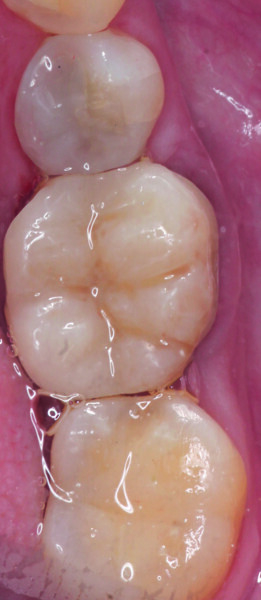

Results and discussion The fully aesthetic and functional results were remarkable and were achieved in a single chairside session, to the full satisfaction of both patient and dentist (Figs. 16–19).

Fig. 16: Astonishing results with excellent marginal adaptation and aesthetics

Fig. 17: Occlusal adjustments and articulation confirming the astonishing results.

Fig. 18: Occlusal view of the excellent final results.